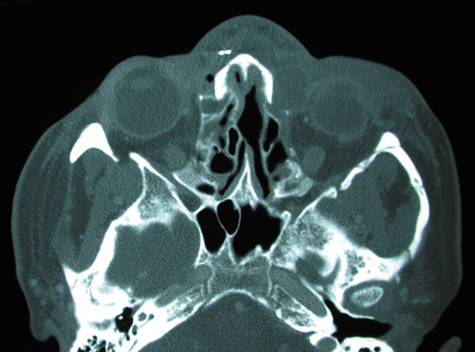

CT is particularly useful for imaging orbital and subperiosteal abscesses. Because the periorbit is not adherent to the orbital walls except at the suture lines, an abscess lifts the periorbit, creating a convexity in the orbital periosteum (Fig. 16). Usually subperiosteal abscess formation occurs adjacent to the involved sinus,25,64 but occasionally it occurs at a remote location such as the superolateral orbit.65 Gas may be found within a subperiosteal abscess or within the orbit, arising either from gas-forming bacilli or free communication with sinus air or from prior trauma (Fig. 17). 57,66 CT cannot accurately predict whether a subperiosteal mass represents exudate, inflammatory transudate, or hematoma.67,68

Fig. 16. Computed tomography showing subperiosteal abscess formation. Note elevation of orbital periosteum and convexity as pus elevates periorbit from the medial orbital wall.

Fig. 17. Intraorbital gas in a 58-year-old patient with orbital cellulitis from a left frontal sinus mucocele. Gas appears as an area of complete radiolucency on this computed tomographic image.

A subperiosteal abscess may rupture or invade the periorbit, resulting in an orbital abscess. This may or may not be contiguous with the subperiosteal collection on CT. There may be gas or air–fluid levels within the mass.51,56,58,59 An orbital abscess may present as an enhancing ringlike peripheral mass that can be either heterogeneous or homogeneous (Fig. 18).

Fig. 18. Orbital abscess. A. Computed tomography of an orbital abscess presenting as an enhancing intraconal mass on right side. B. T1-weighted image. C. T2-weighted image. Note area of high signal corresponding to abscess.